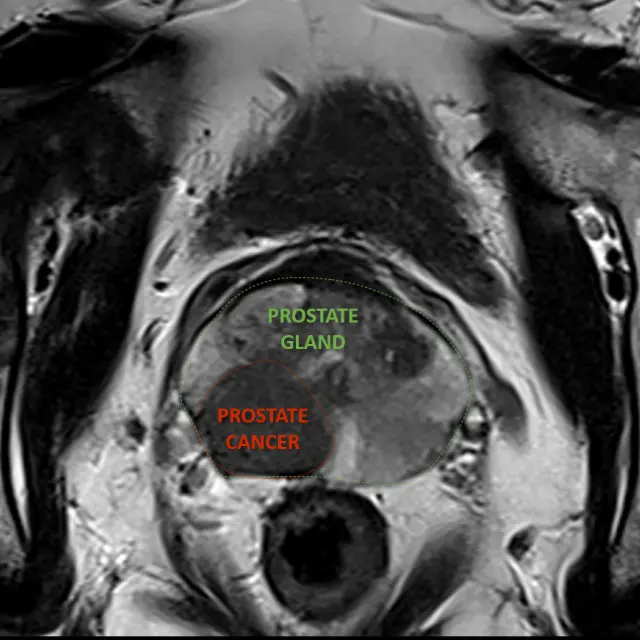

Canopy news Latest news and info from Canopy Healthcare December 01 2025 Canopy Imaging Brings Cutting-Edge, Sustainable MRI Technology to Ormiston MRI Sustainability Canopy Imaging is proud to announce the installation of the MAGNETOM Vida Fit, a state-of-the-art 3T MRI system from Siemens Healthineers, at its Ormiston Canopy Imaging Clinic in Auckland. Read more May 21 2025 Understanding Pelvic Floor Disorders and how Canopy Imaging can help MRI Pelvic Floor Pelvic floor disorders affect up to 25% of women. They often present with incontinence, organ prolapse, and difficulty defaecating (passing stools). Read more April 15 2025 Your MRI Experience at Canopy Imaging MRI We understand that undergoing your first MRI scan can be an unfamiliar and potentially unsettling experience. Read more July 02 2024 Canopy Imaging – Kerikeri’s New MRI Patient Experience Kerikeri MRI Our first Canopy Imaging clinic recently opened in Kerikeri, marking the first steps in rebranding all TRG Imaging diagnostic clinics in the North Island. Read more September 18 2023 Unlocking the Advantages of Magnetic Resonance Imaging for Prostate Cancer MRI Prostate cancer Read more June 26 2023 Your First MRI Scan: Comfort and Care Await MRI Patient Safety Read more June 13 2023 Canopy Imaging (formerly TRG Imaging) Northland expands with state-of-the-art technologies CT Kerikeri MRI Whangārei Read more May 29 2023 Hawke’s Bay benefits from ongoing investment in local radiology and cancer treatment services Hawke’s Bay MRI PET/CT SPECT/CT Read more